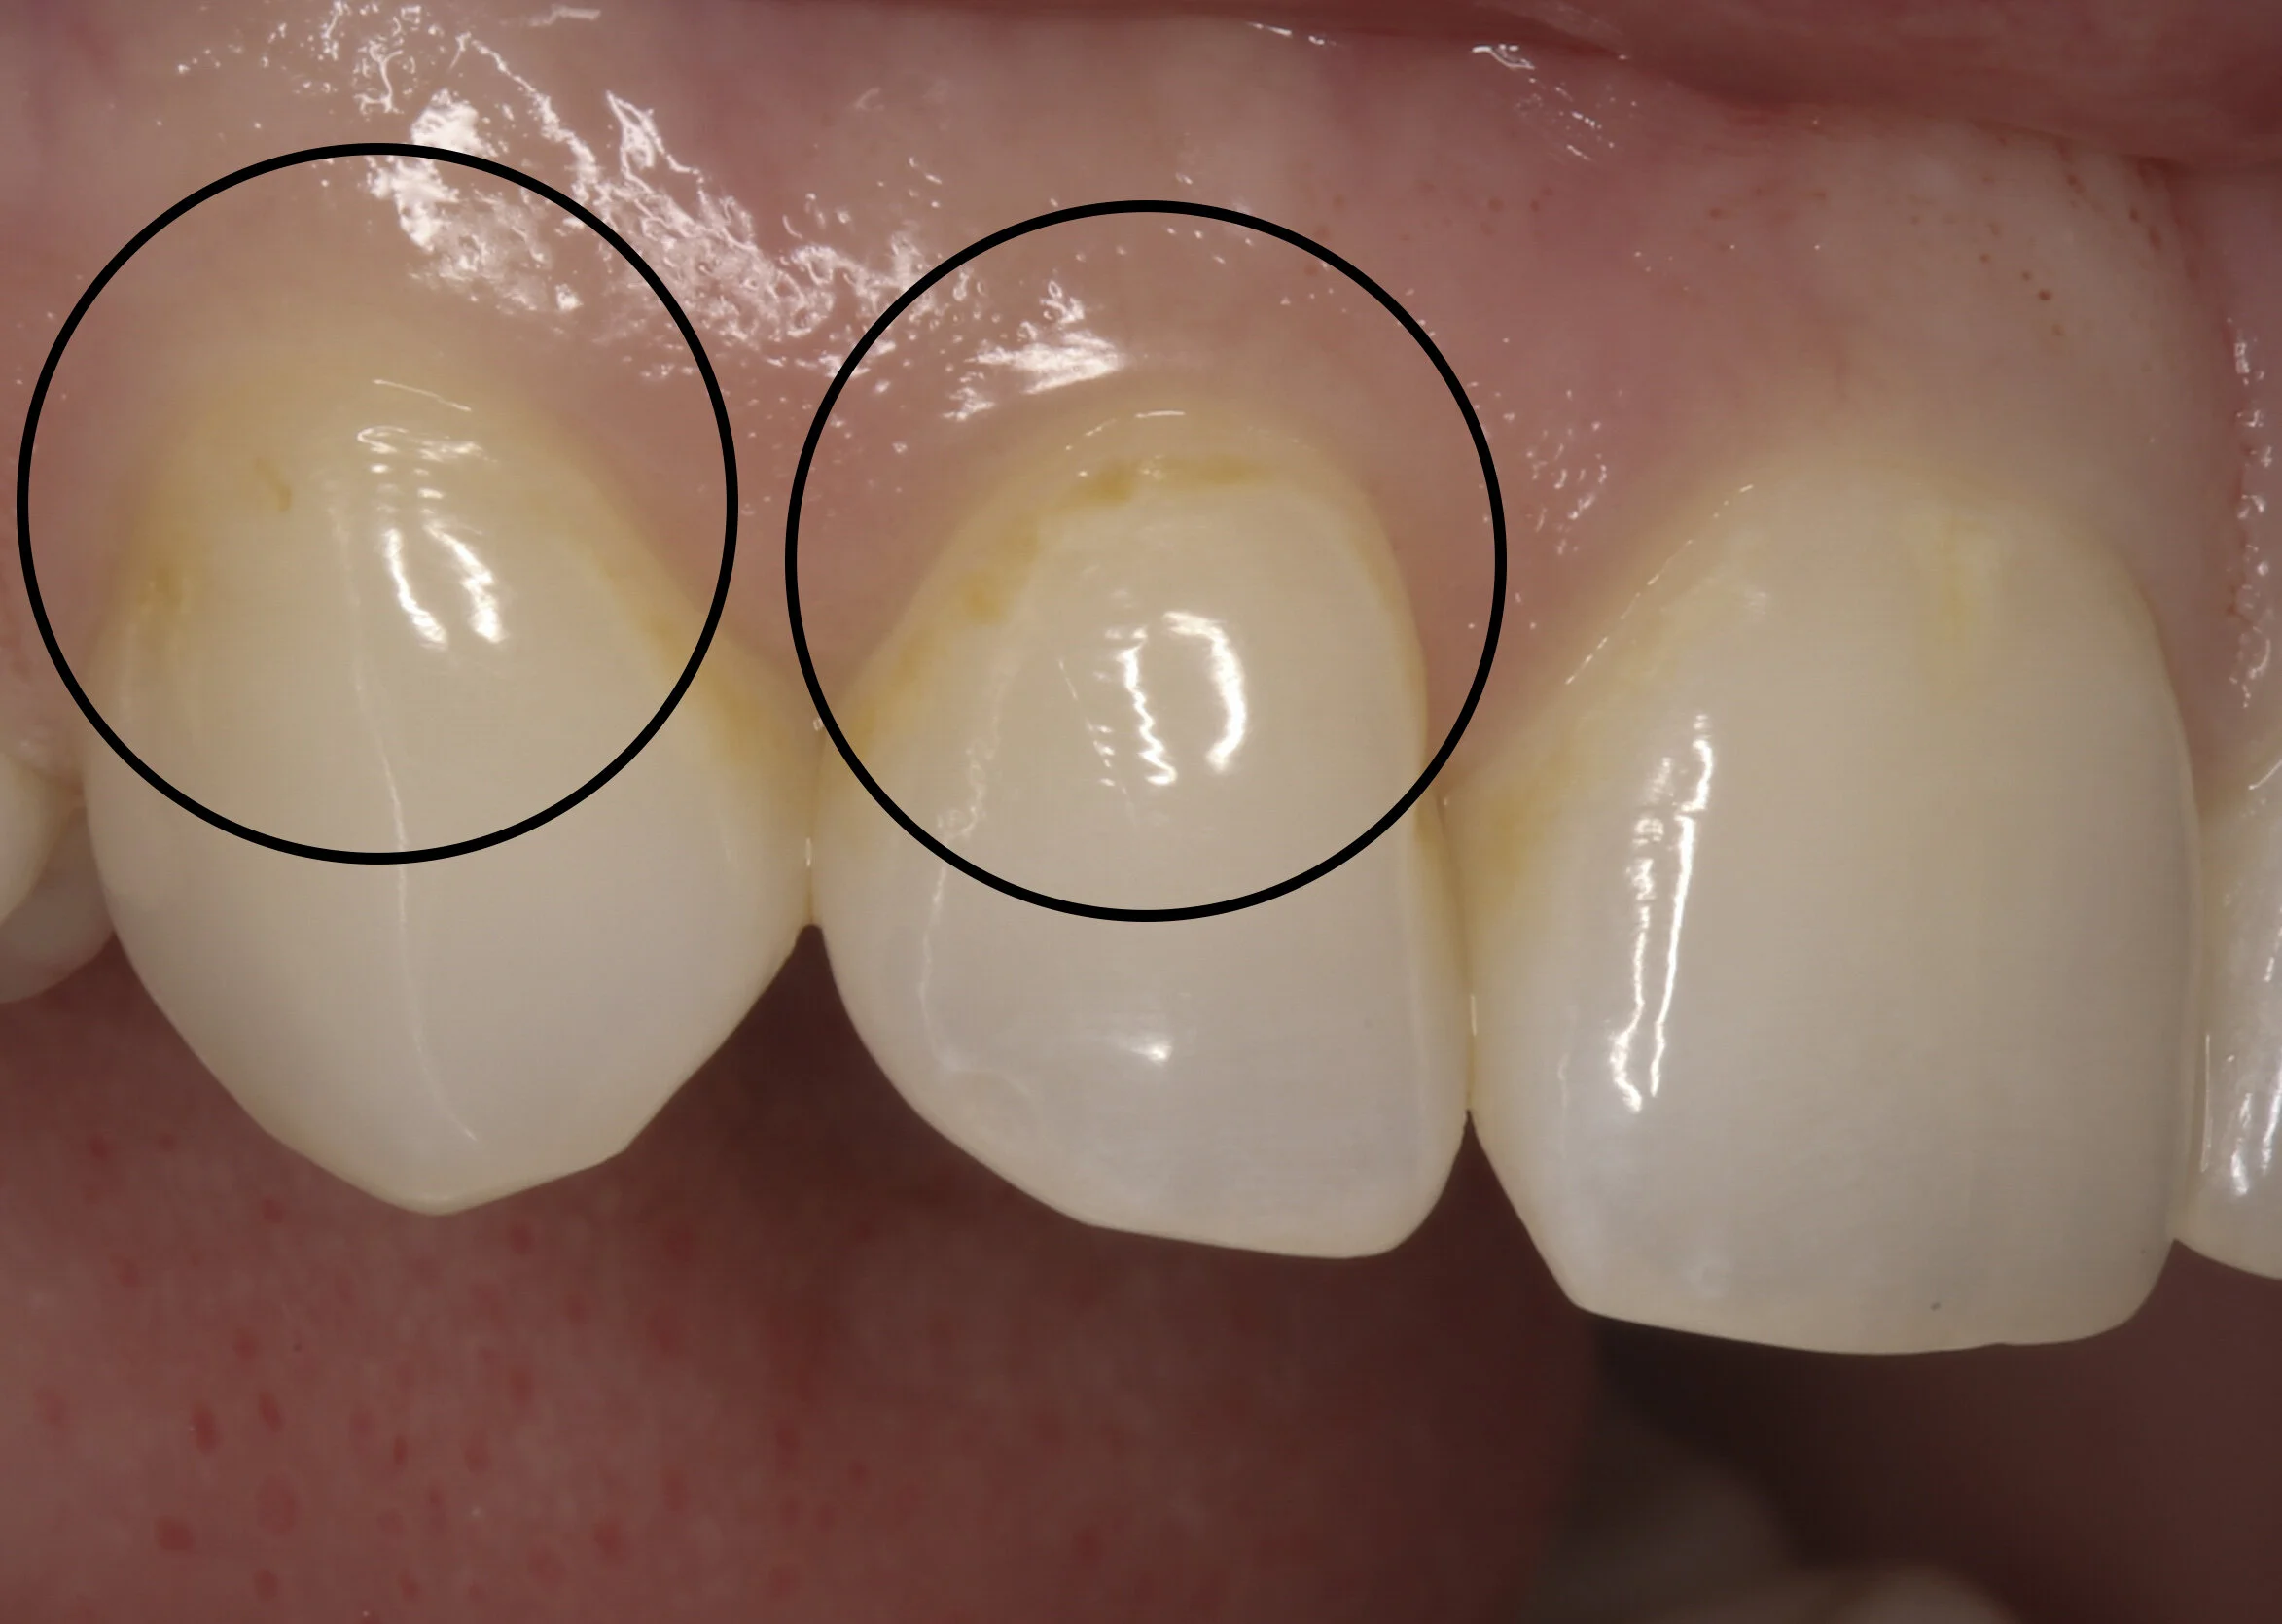

White Fillings Before and After photos Front Tooth Composite Fillings Composite Filling Side Effects Composite fillings, when well cared for, can last between 7 and 10 years, while. Composite resin dental fillings may be more prone to cracking, breaking, and wearing out than metal fillings, and over time leaks may develop in. These may wear and chip over. Less durability than metal (amalgam or gold) fillings, which can last decades. They can be matched. Composite Filling Side Effects.